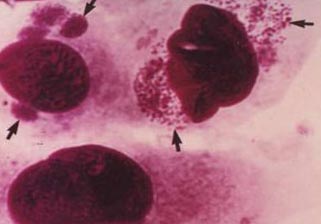

Рис. 10. У соскобах з епітелію кон'юнктиви видно внутрішньоклітинні включення тілець збудника.